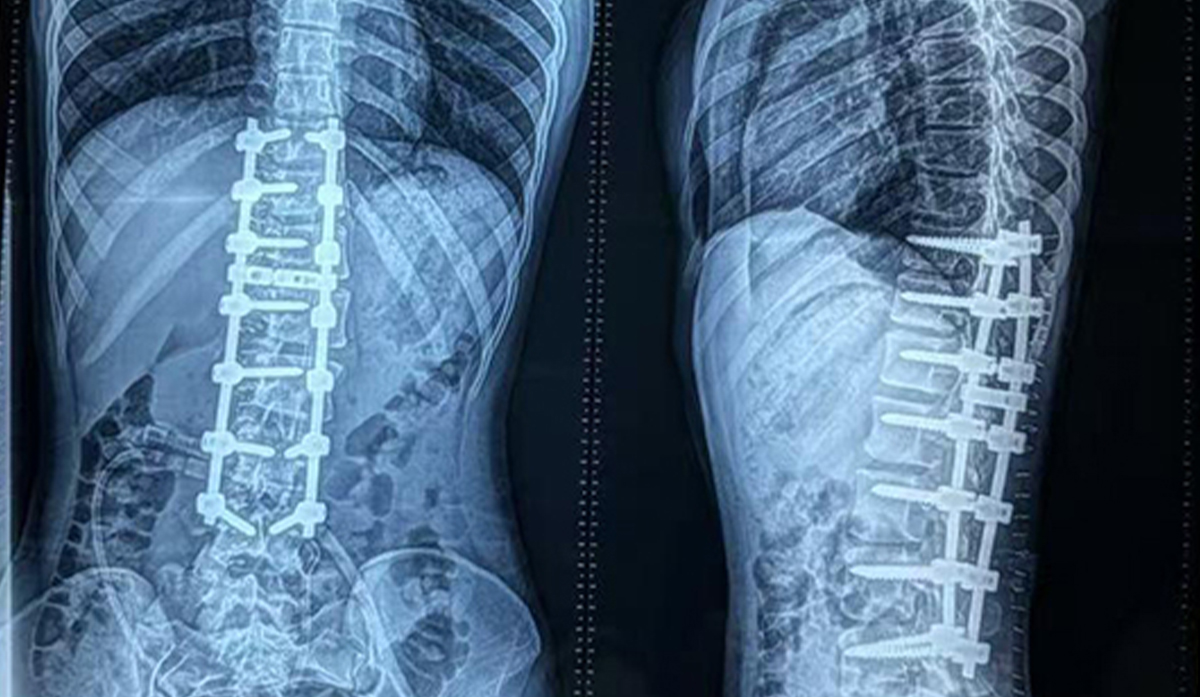

• Skolioosin korjausleikkaus Bangladeshissa: 6,0 mm:n selkärangan pedicle-ruuvijärjestelmä

16-vuotiaalle skolioosipotilaalle Dhakassa, Bangladeshissa, tehtiin selkärangan epämuodostuman korjaus käyttämällä 6,0 mm:n selkärangan pedicle-ruuvijärjestelmää, mikä saavutti kolmiulotteisen korjauksen, vakaan kiinnityksen ja sujuvan palautumisen.

• Tapaustutkimus: Skolioosin korjausleikkaus Dhakassa, Bangladeshissa 6,0 mm:n pedicle-ruuvijärjestelmällä

Skolioosin korjausleikkaus Dhakassa, Bangladeshissa, jossa käytettiin 6,0 mm:n pedicle-ruuvijärjestelmää, saavutti vakaan kiinnityksen ja paransi selkärangan kohdistusta nuorella potilaalla.